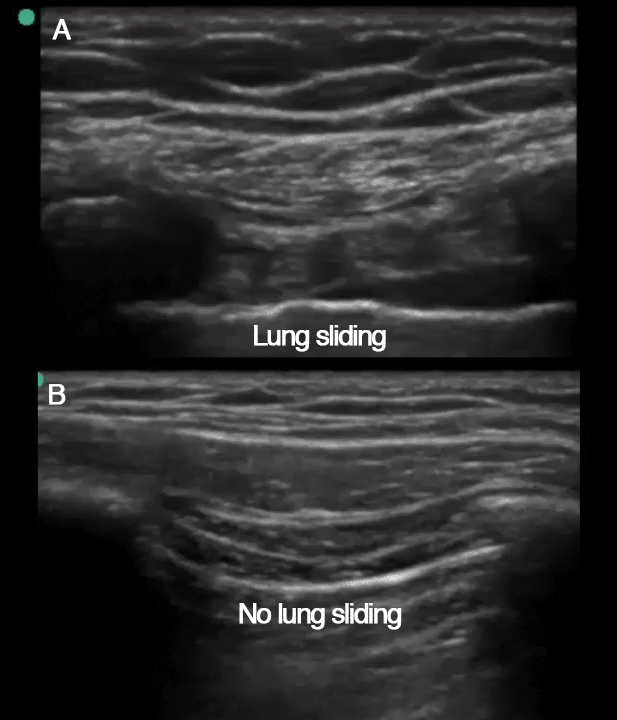

Top: Normal lung with sliding and B-lines present.

Bottom: No sliding, no lung pulse, and no B-lines — possible pneumothorax.